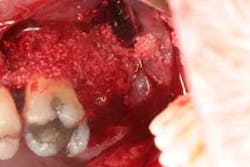

Figures 6a and 6b: Osseous surgery in the upper left quadrant with debridement of root surfaces, extraction of No. 15, and then regeneration.

Briefly, during osseous surgery, the upper right molars were treated with a combination of autograft and platelet-derived growth factor/Beta-tricalcium phosphate along with a porcine collagen graft (figures 5a and 5b). The upper left osseous surgery consisted of the same treatment (figures 6a and 6b), but also included the extraction of a hopeless tooth No. 15. Once again, the anterior osseous surgery consisted of the same regenerative materials as the former surgeries but with the addition of a porcine soft-tissue graft (figures 7a, 7b, and 7c). After the initial healing phase, the patient was placed on a strict home-care regimen and was seen every eight to 12 weeks for hygiene recare. The patient maintained excellent hygiene throughout the five-year follow-up period.